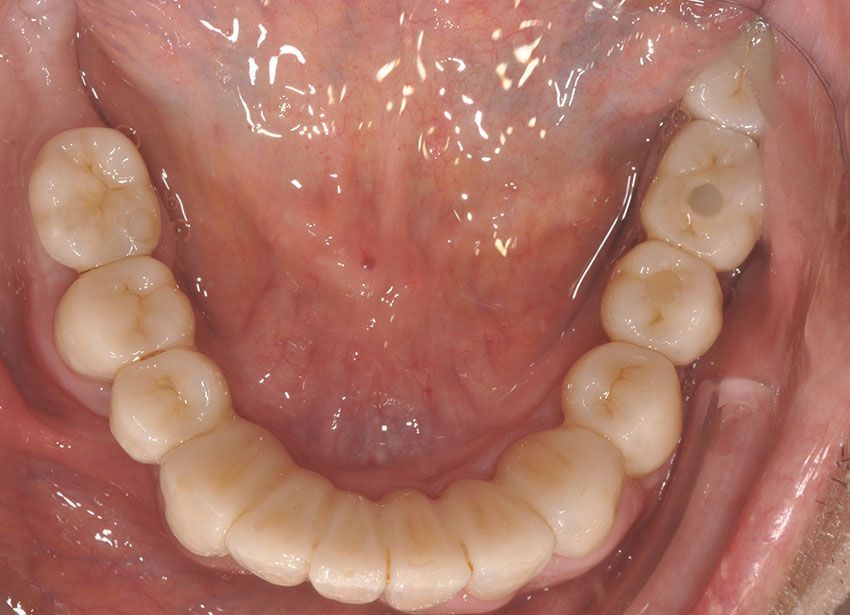

Sia per la realizzazione di corone su impianti osteointegrati che su dente naturale, usiamo la tecnologia digitale CAD/CAM: si progetta il restauro su un modello 3D ricavato da una scansione intra-orale, sul quale viene realizzato un manufatto ad alta precisione, con risultati estetici impareggiabili, incrementando il comfort per il paziente.

Dì addio alle impronte tradizionali!

Diresti mai che è una protesi?

Ogni manufatto viene studiato sulla base delle caratteristiche del volto, del sorriso e dell’occlusione, per restituire funzionalità e comfort, esaudendo le aspettative estetiche di ogni paziente.

Le protesi fisse su impianti in particolare, offrono stabilità nel tempo, una resa estetica elevata, una sensazione naturale durante la masticazione, nonché l'integrazione ottimale con denti e tessuti. Il paziente viene accompagnato in ogni fase, dalla pianificazione alla finalizzazione del lavoro, con